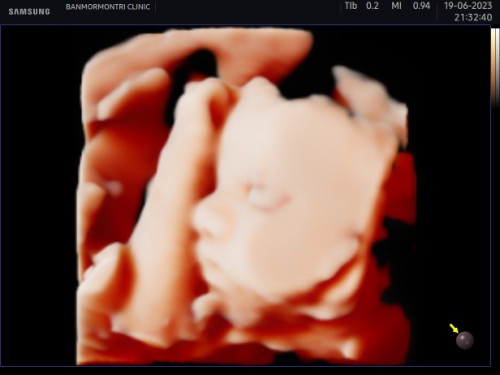

ลูกสาวคนแรก

29 วีค +2 น้ำหนัก 1200 กรัม แม่ๆกินอารัยบำรุงค่ะ อยากให้น้ำหนักสาวน้อยเพิ่มอีกนิด#ขอบคุณล่วงหน้านะคะ

บ้านนี้กินไข่ต้มวันล่ะฟอง กินกล้วยน้ำหว้า นมแพะค่ะและกินจุกจิกกินข้าวน้อยๆแต่กินหลายรอบเพราะหมอบอกถ้ากินข้าวมื้อใหญ่เลยจะไม่ค่อยลงลูกจะลงแม่ค่ะ ตอนนี้29วีคน้ำหนักแม่ขึ้นแค่1โลค่ะส่วนเจ้าตัวน้อย1700กรัมค่ะ